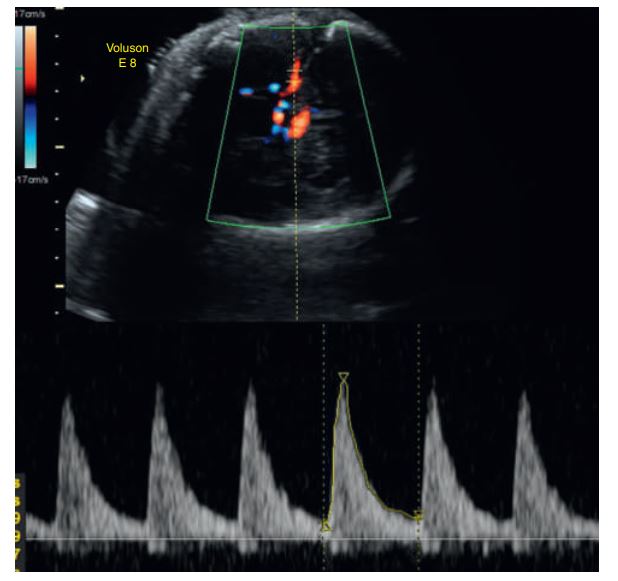

During the fetal cardiac cycle, there is umbilical blood flow during both the pumping (systole) and filling (diastole) phases of the heartbeat.

No flow (absent end-diastolic flow) and_______ during diastole .

signs of fetal jeopardy and may prompt the obstetrician to do further fetal well-being testing or even to deliver the fetuses.

Reversal of diastolic flow in a twin gestation with twin-totwin transfusion syndrome.